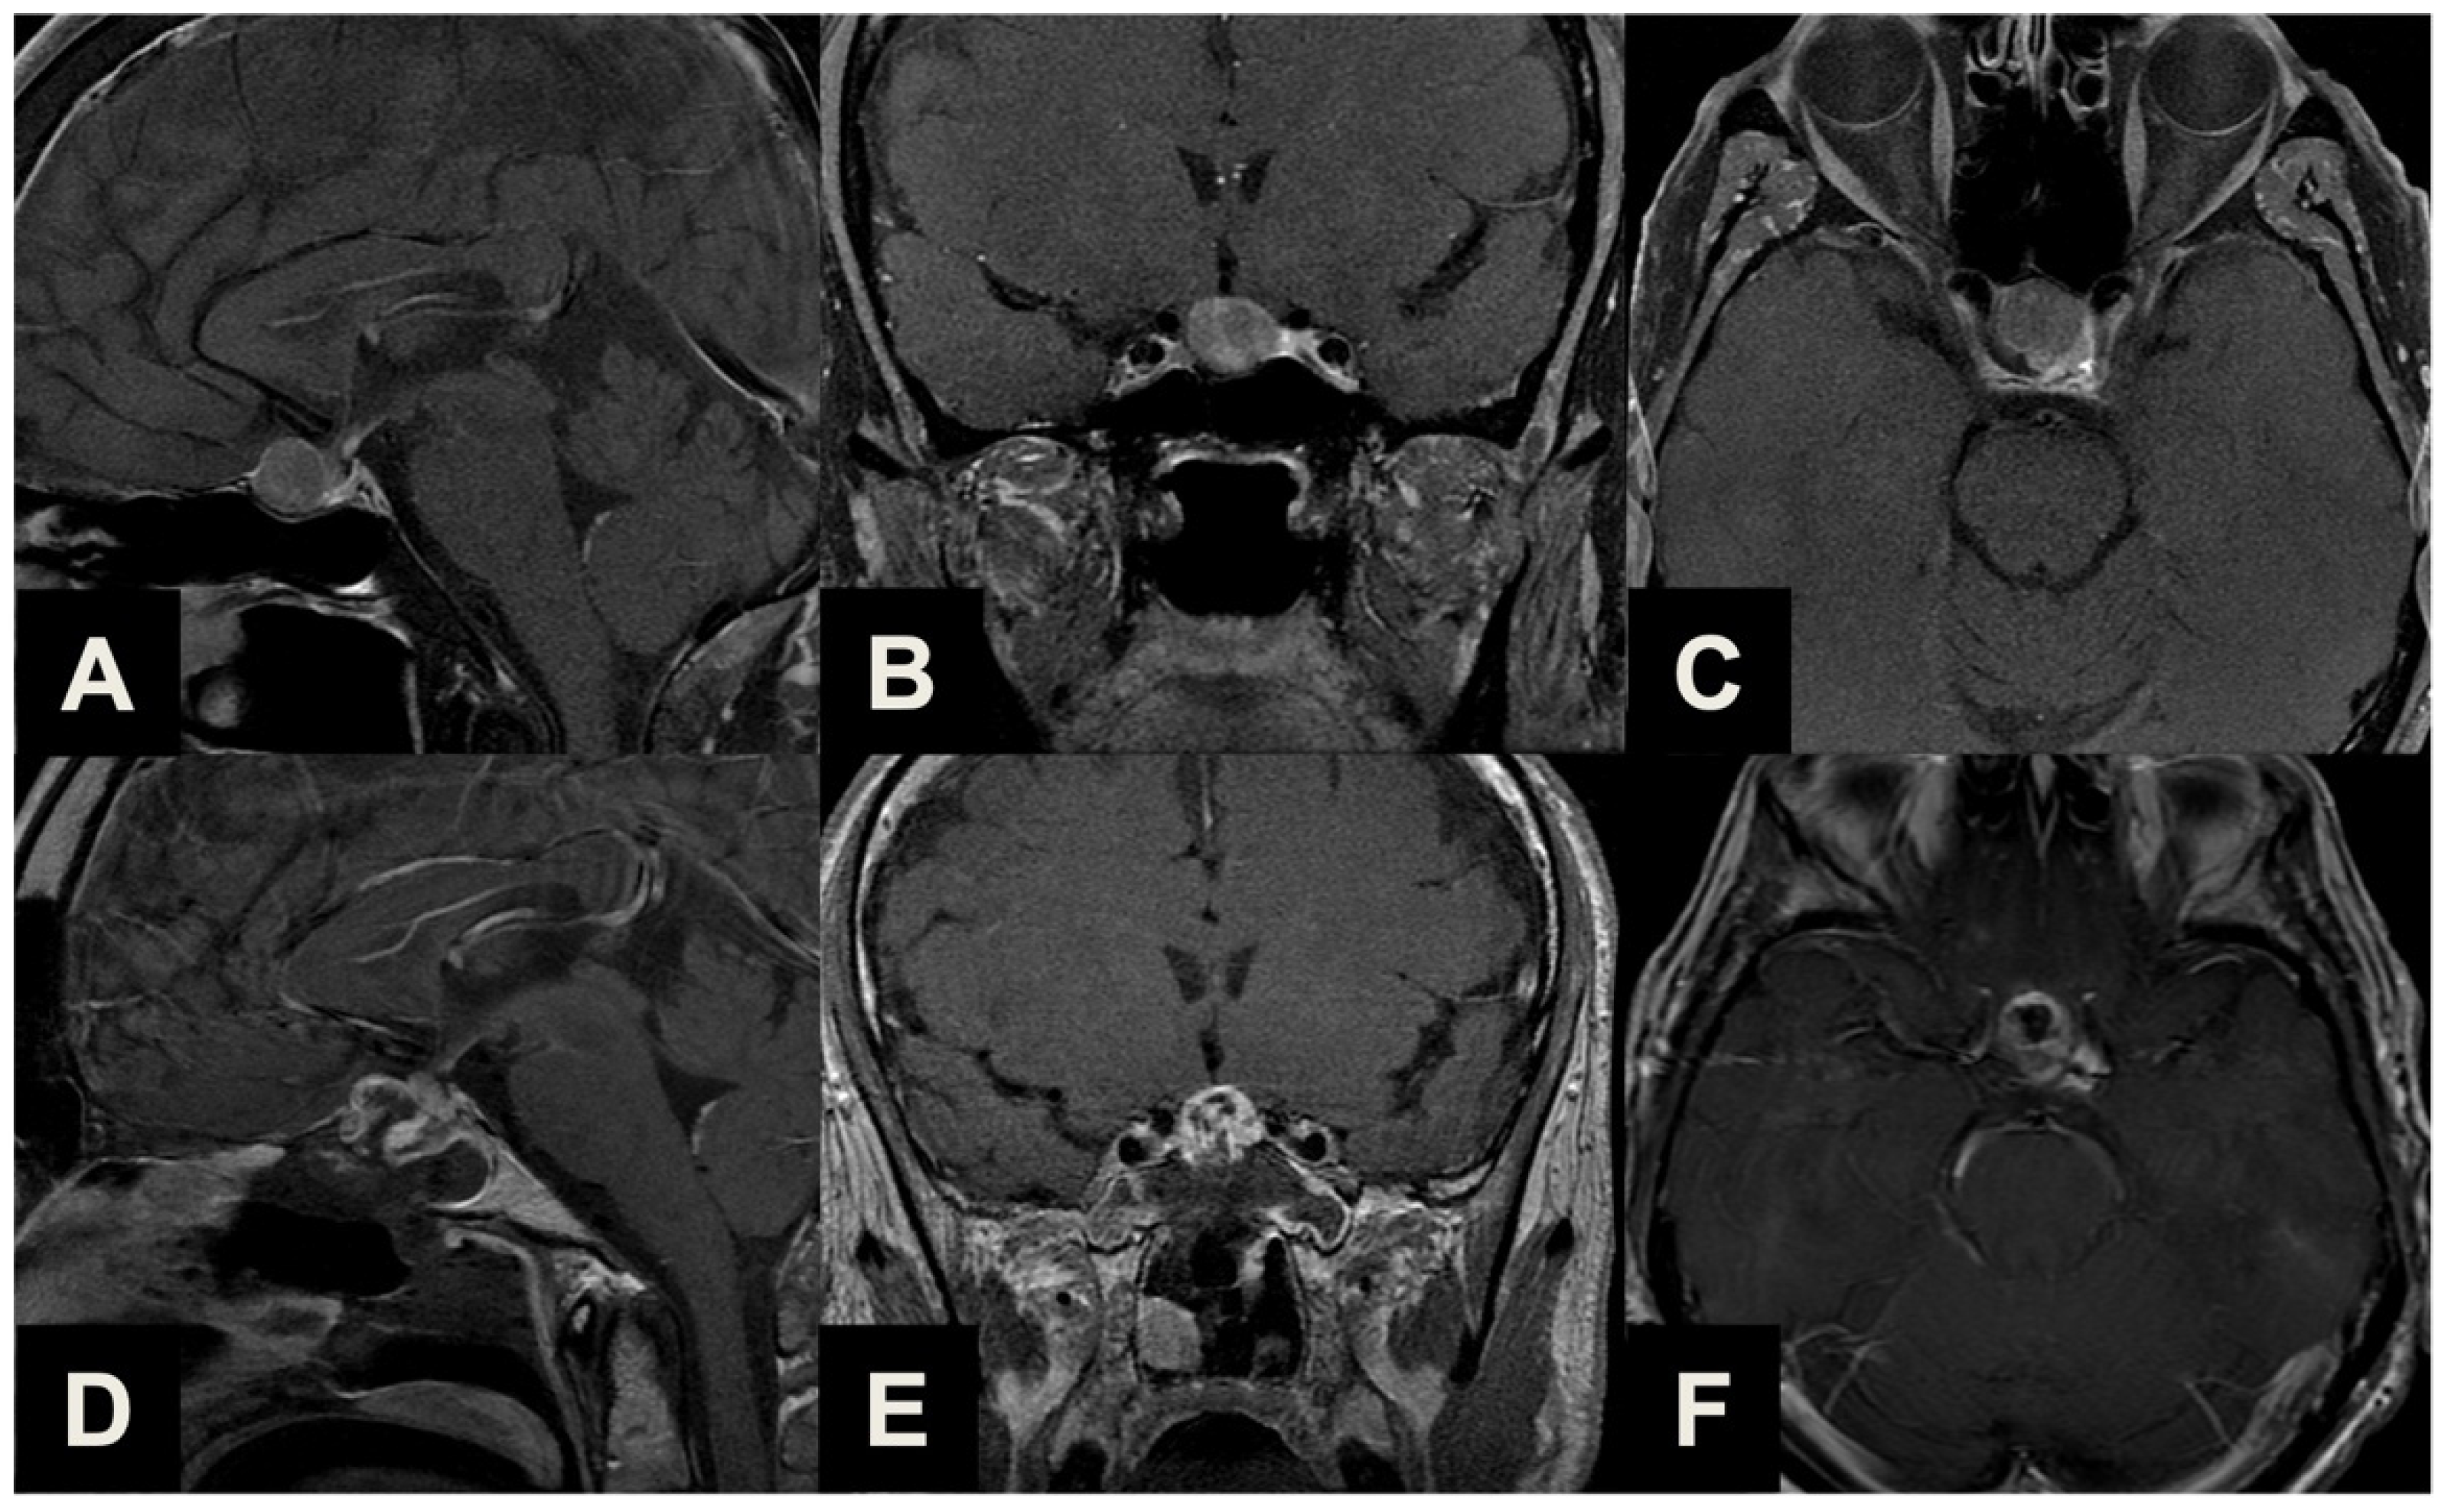

| Type 1 | Ectopic peduncular or supradiaphragmatic peri-infundibular PAs, including ectopic microadenomas of the pituitary stalk or purely supradiaphragmatic macroadenomas (mostly remnant or recurrence after previous partial surgeries). These tumors are not suitable for an EEA because they have no sellar infradiaphragmatic component. |

| Type 2 | PAs with sub-frontal extension, including macroadenomas with a supra- or infradiaphragmatic sub-frontal extension. These tumors are not fully resectable with an EEA because of their sub-frontal component, which extends anteriorly with an unfavorable angle and direction for the trans-sphenoidal approach. |

| Type 3 | PAs presenting with a major extrasellar component, including macroadenomas with suprasellar supradiaphragmatic component exceeding the sellar volume (i.e., air balloon PAs) unlikely to be delivered through the sella with an EEA, and macroadenomas with both a large intrasellar infradiaphragmatic part and a large suprasellar supradiaphragmatic portion connected through a narrow isthmus (i.e., snowman PAs), which impairs their resection through an EEA. |